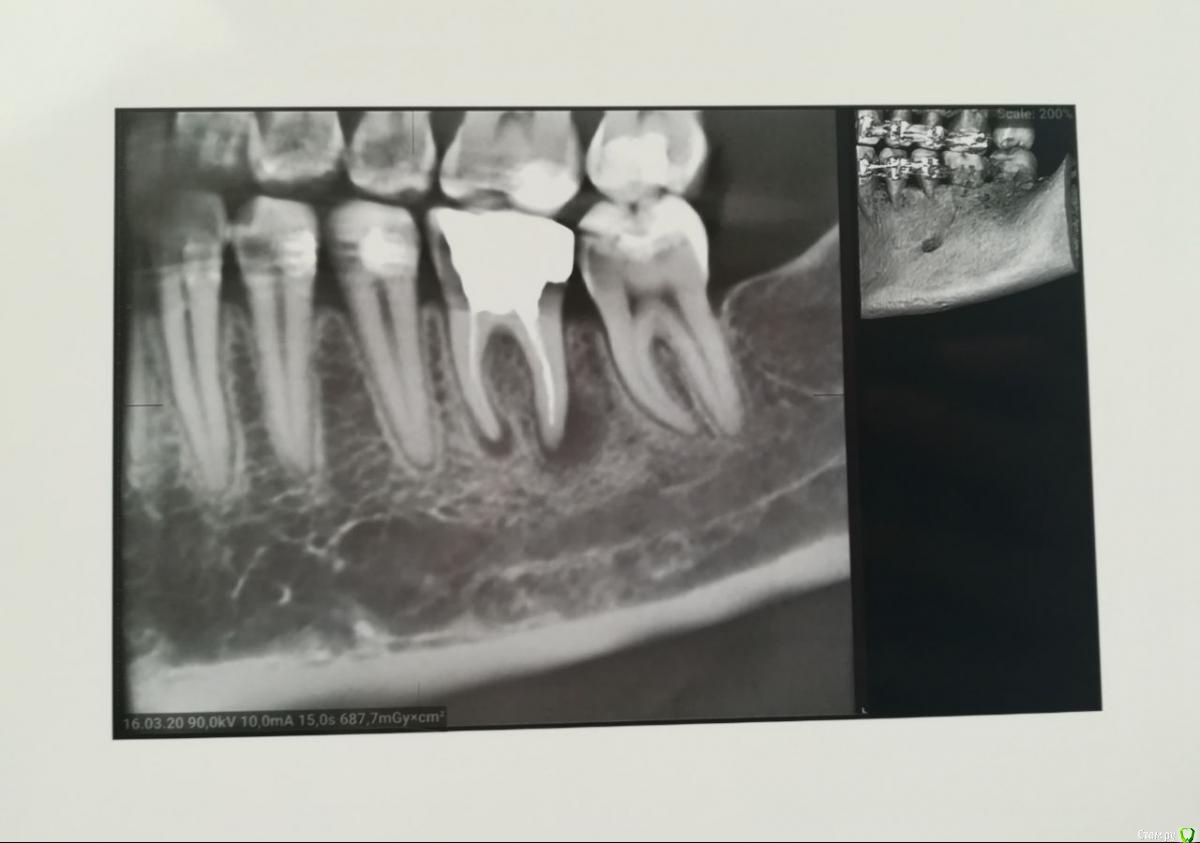

Tansky Опубликовано 18 марта, 2020 Автор Поделиться Опубликовано 18 марта, 2020 снимки - пара отпг до орто и актуальная, от 17.03.2020пара кт, в области интереса 3.6 и 4.7, разные снимки Ссылка на комментарий

Tansky Опубликовано 18 марта, 2020 Автор Поделиться Опубликовано 18 марта, 2020 разные проекции и описание заключения. прицельные rg есть еще по тому же зубу разных времен, но это надо искать дома и фоткать с негатоскопа или днем на свет Ссылка на комментарий